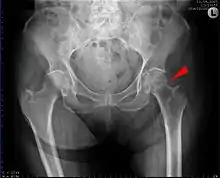

Intertrochanteric hip fracture in a 17-year-old male

X-rays of the affected hip usually make the diagnosis obvious; AP (anteroposterior) and lateral views should be obtained.